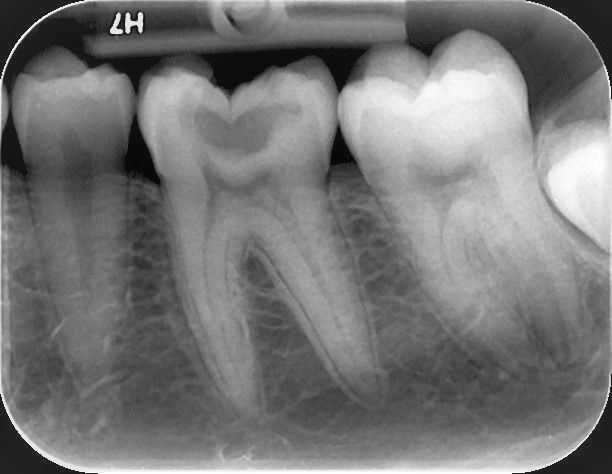

Η οπισθοφατνιακή ακτινογραφία λαμβάνεται με την τοποθέτηση του ακτινογραφικού πλακιδίου εσωτερικά των δοντιών (προς την πλευρά της γλώσσας ή του ουρανίσκου) και παράλληλα με αυτά. Χρησιμοποιείται ειδικός συγκρατητήρας του φιλμ, τον οποίο δαγκώνει ο εξεταζόμενος. Με αυτή απεικονίζονται ένα ή περισσότερα δόντια (τόσο η μύλη, όσο και η ρίζα αυτών), καθώς και τμήμα του φατνιακού οστού που περιβάλλει τις ρίζες των δοντιών. Αποτελεί την πιο απλή οδοντιατρική ακτινογραφική απεικόνιση. Χρησιμοποιούνται τρία μεγέθη φιλμ ή πλακιδίου ανάλογα με την περιοχή που θέλουμε να απεικονιστεί, το μέγεθος του στόματος του εξεταζόμενου και την ηλικία του. Η λήψη της είναι γρήγορη (διαρκεί λίγα δευτερόλεπτα) και ανώδυνη.

Η οπισθοφατνιακή ακτινογραφία μεταξύ άλλων μας επιτρέπει:

• την ανίχνευση οδοντικών τερηδόνων, τον καθορισμό της έκτασης και του βάθους τους και της σχέσης τους με τον πολφό του δοντιού

• τη μελέτη των ριζών των δοντιών (αριθμός, μορφολογία και πιθανή κάμψη αυτών, ύπαρξη απορρόφησης ή κατάγματος)

• τη μελέτη του αριθμού, της μορφολογίας, του εύρους και της πορείας των ριζικών σωλήνων εντός των ριζών

• τη μελέτη των σκληρών ιστών του περιοδοντίου, δηλαδή του φατνιακού οστού που περιβάλλει και στηρίζει το δόντι και του περιοδοντικού συνδέσμου. Σε περίπτωση περιοδοντικής νόσου, καθορίζεται η εντόπιση, ο βαθμός και η φύση (οριζόντια, γωνιώδης) της απορρόφησης του φατνιακού οστού

• τη μελέτη του φατνιακού οστού της περιακρορριζικής περιοχής του δοντιού για ύπαρξη παθολογικών εξεργασιών (απόστημα, κοκκίωμα, κύστη κ.λ.π.)

• την ανίχνευση κατάγματος των δοντιών.